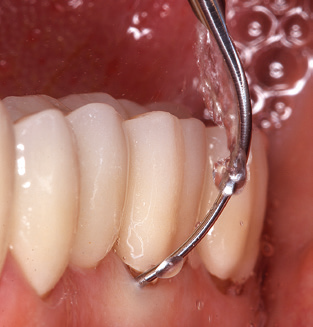

Naturalmente, anche i consigli di lavoro per la pulizia delle superfici degli impianti sono indispensabili per SPT nei pazienti dotati di impianti. L'inserto per la pulizia dell'impianto in questo casoi è caratterizzato dal suo design affusolato ed esagonale. Questo design consente una penetrazione leggera e atraumatica nella tasca perimplantare e mostra buone prestazioni di pulizia (Fig. 7).